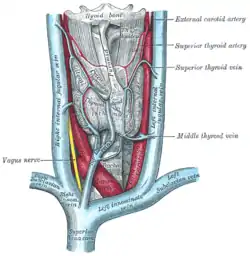

The fascia and middle thyroid veins. (Superior thyroid artery labelled at upper left.) | |

| Vein | superior thyroid vein |